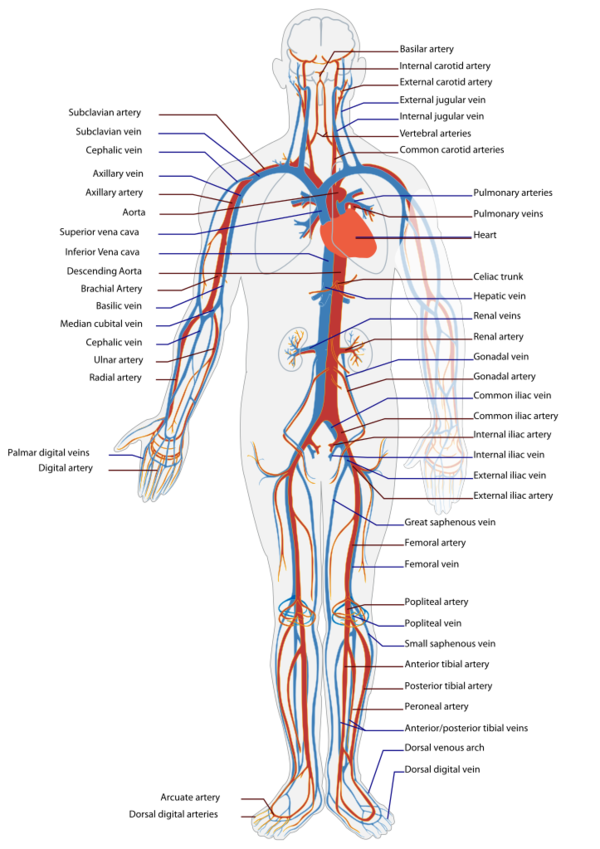

Cardiovascular physiology is the study of the cardiovascular system, specifically addressing the physiology of the heart (cardiac physiology) and blood vessels (circulatory physiologic) (see figure 16[95]). The cardiovascular system is a pressurized closed system responsible for transporting nutrients, hormones, and cellular waste throughout the body. From a physical point of view, there are three independent circuits:

This monograph will focus on systemic arterial system and coronary circulation.

The blood vessels are the part of the circulatory system that transport blood throughout the body. The vascular system is composed of arteries, arterioles, capillaries, venules and veins (see figure 17[96]). The three main types of blood vessels are:

- Arteries, which carry blood away from the heart at relatively high pressure,

- Veins, which carry blood back to the heart at relatively low pressure and

- Capillaries, which provide the link between the arterial and venous blood vessels.

Regarding the small vessels mention that arterioles are the smallest branches of the arterial network. Arterioles vary in diameter ranging from 0.3 mm to 0.4 mm. Any artery with a diameter smaller than 0.5 mm is considered to be an arteriole. Capillaries are specialized for diffusion of substances across their wall. Capillaries are the smallest vessels of the blood circulatory system and form a complex inter linking network. Pressure is essentially lost in the capillaries. As the capillaries begin to thicken and merge, they become venules. Venules eventually become veins and head back to the heart.

In general, arteries are roughly subdivided into two types: elastic (or large arteries) and muscular (or small arteries). Elastic arteries have relatively large diameters and are located close to the heart (for example, the aorta, the carotid and iliac arteries), while muscular arteries are located at the periphery (for example, femoral, celiac, cerebral arteries). The walls of all the blood vessels, except the capillaries which are only one cell thick, have the same basic components but the proportion of the components varies with function. Therefore, the structure of the vessels in the different parts of the circulatory or vascular system varies and the differences relate directly to the function of each type of vessel (see table 2). Arteries are not just tubes through which the blood flows.